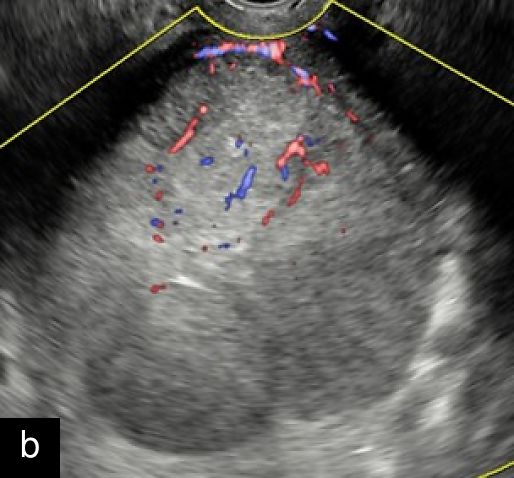

2

Transvaginal ultrasound images with color Doppler of uterine sarcoma, demonstrating heterogeneous echotexture and irregular margins. The Doppler assessment reveals variable vascularization patterns, ranging from moderate (a–b) to extensive (c) intralesional blood flow. Images (b) and (c) show the 'cooked appearance' of solid tissue, a sonographic feature defined by the lack of structure of the solid component and the absence of acoustic shadowing.